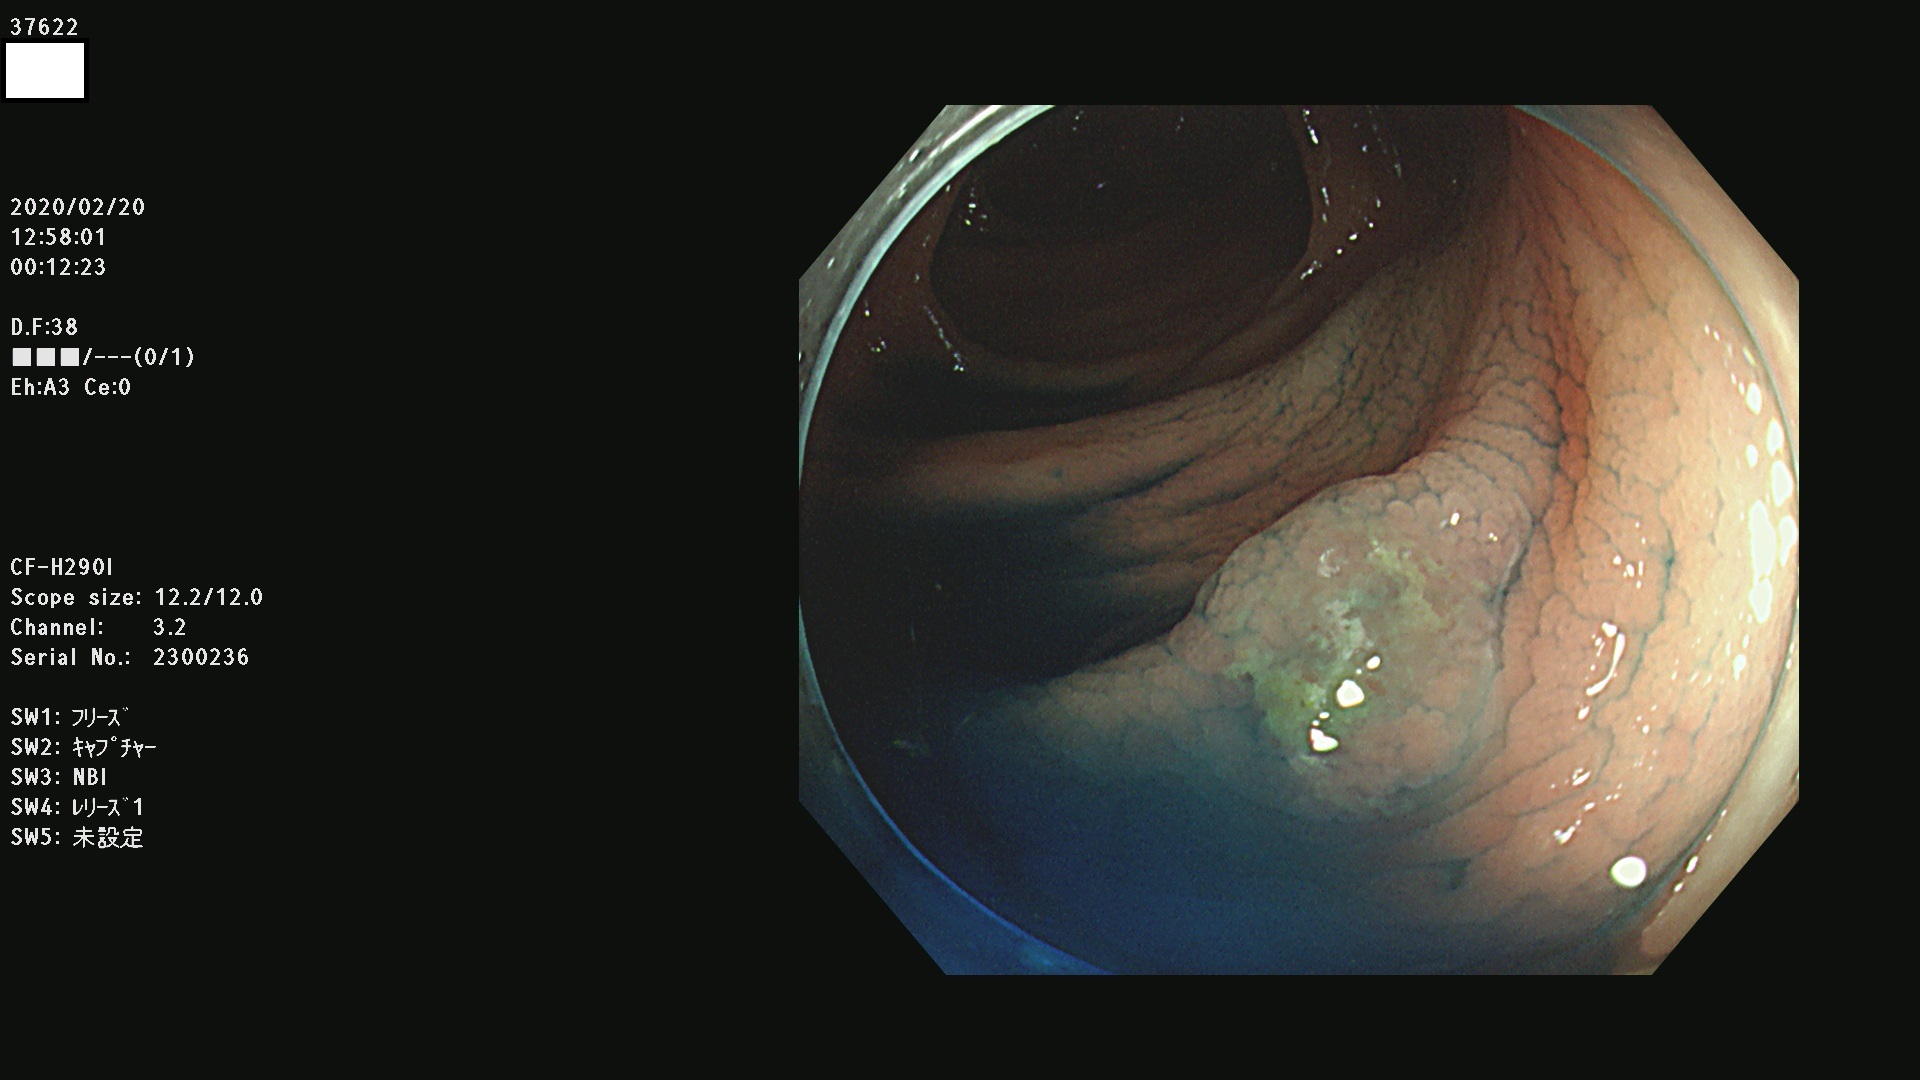

37600 37601 37602 37603 37604 37605 37606 37607 37608 37612 37614 37616 37618 37619 37620 37621 37622(SSAPのみ) 37623(SSAPのみ) 37624 37626 37627 37628 37629 37632 37633 37635 37636(SSAPのみ) 37639 37640 37641 37642 37643 37644 37647(SSAPのみ) 37648 37649 37650 37652 37653 37655 37657 37659 37660 37662 37664 37666 37668(SSAPのみ) 37670 37671 37672 37676 37677 37678 37679 37680 37682 37684 37685(SSAPのみ) 37686 37687 37688 37689 37690 37691 37692(SSAPのみ) 37693 37694 37695 37696 37697 37699

発見困難で危険性の高い平坦型病変(上記100名より抽出)